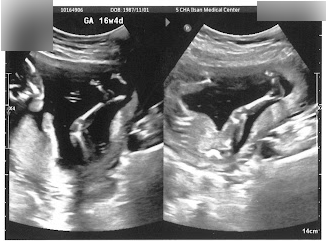

[임신 15 ~ 16주] 임신초기 막바지! 몸무게, 배크기 변화, 임신 적응 과도기, 라이브 클럽 공연 관람, 정기검진, 신경관결손, TSH 2차 검사

임신 29주차에 숙제처럼 쓰는 15주차 일기.. 출산전에 다 쓸 수 있을까...? ㅋㅋㅋㅋㅋ 나중에 콩이랑도 읽...